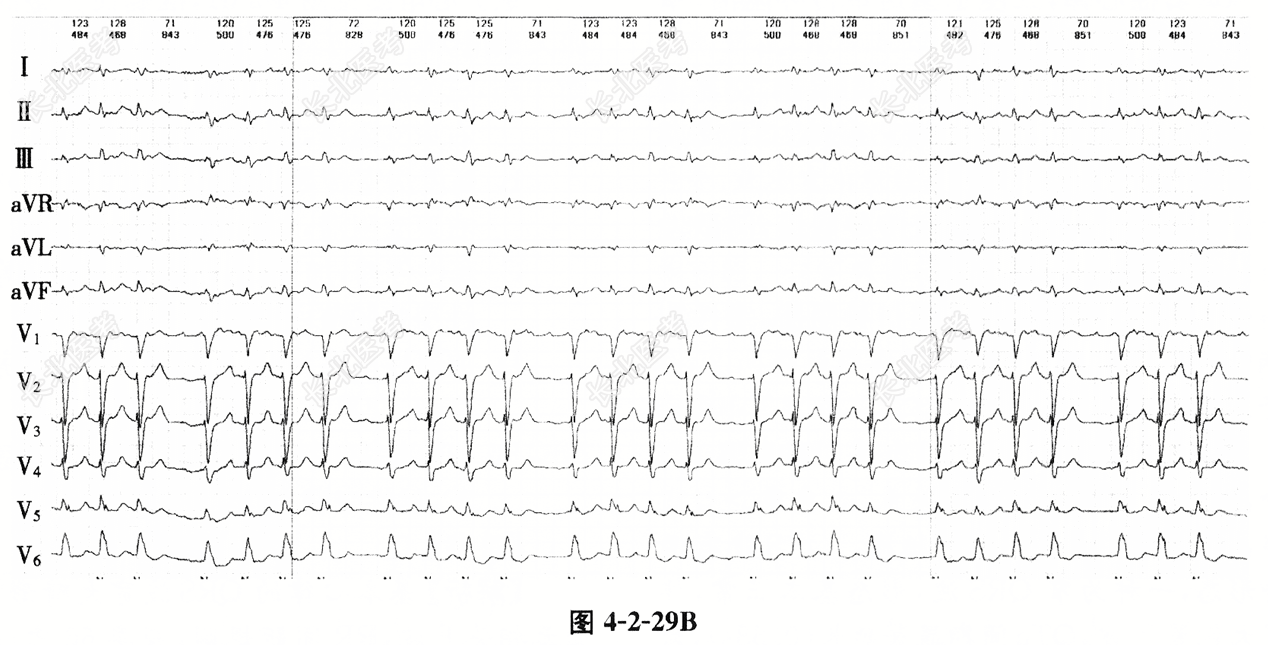

- 单项选择题患者,女, 49岁,因胸闷1周入院。既往有风湿性心脏病、高血压病、2型糖尿病史。结合心电图4-2-29A和4-2-29B, 正确的诊断是

A、心房扑动,间歇性心室预激

B、心房扑动伴3相左束支阻滞

C、心房颤动伴心室内差异性传导

D、心房扑动伴心室内差异性传导

E、心房颤动,室性期前收缩